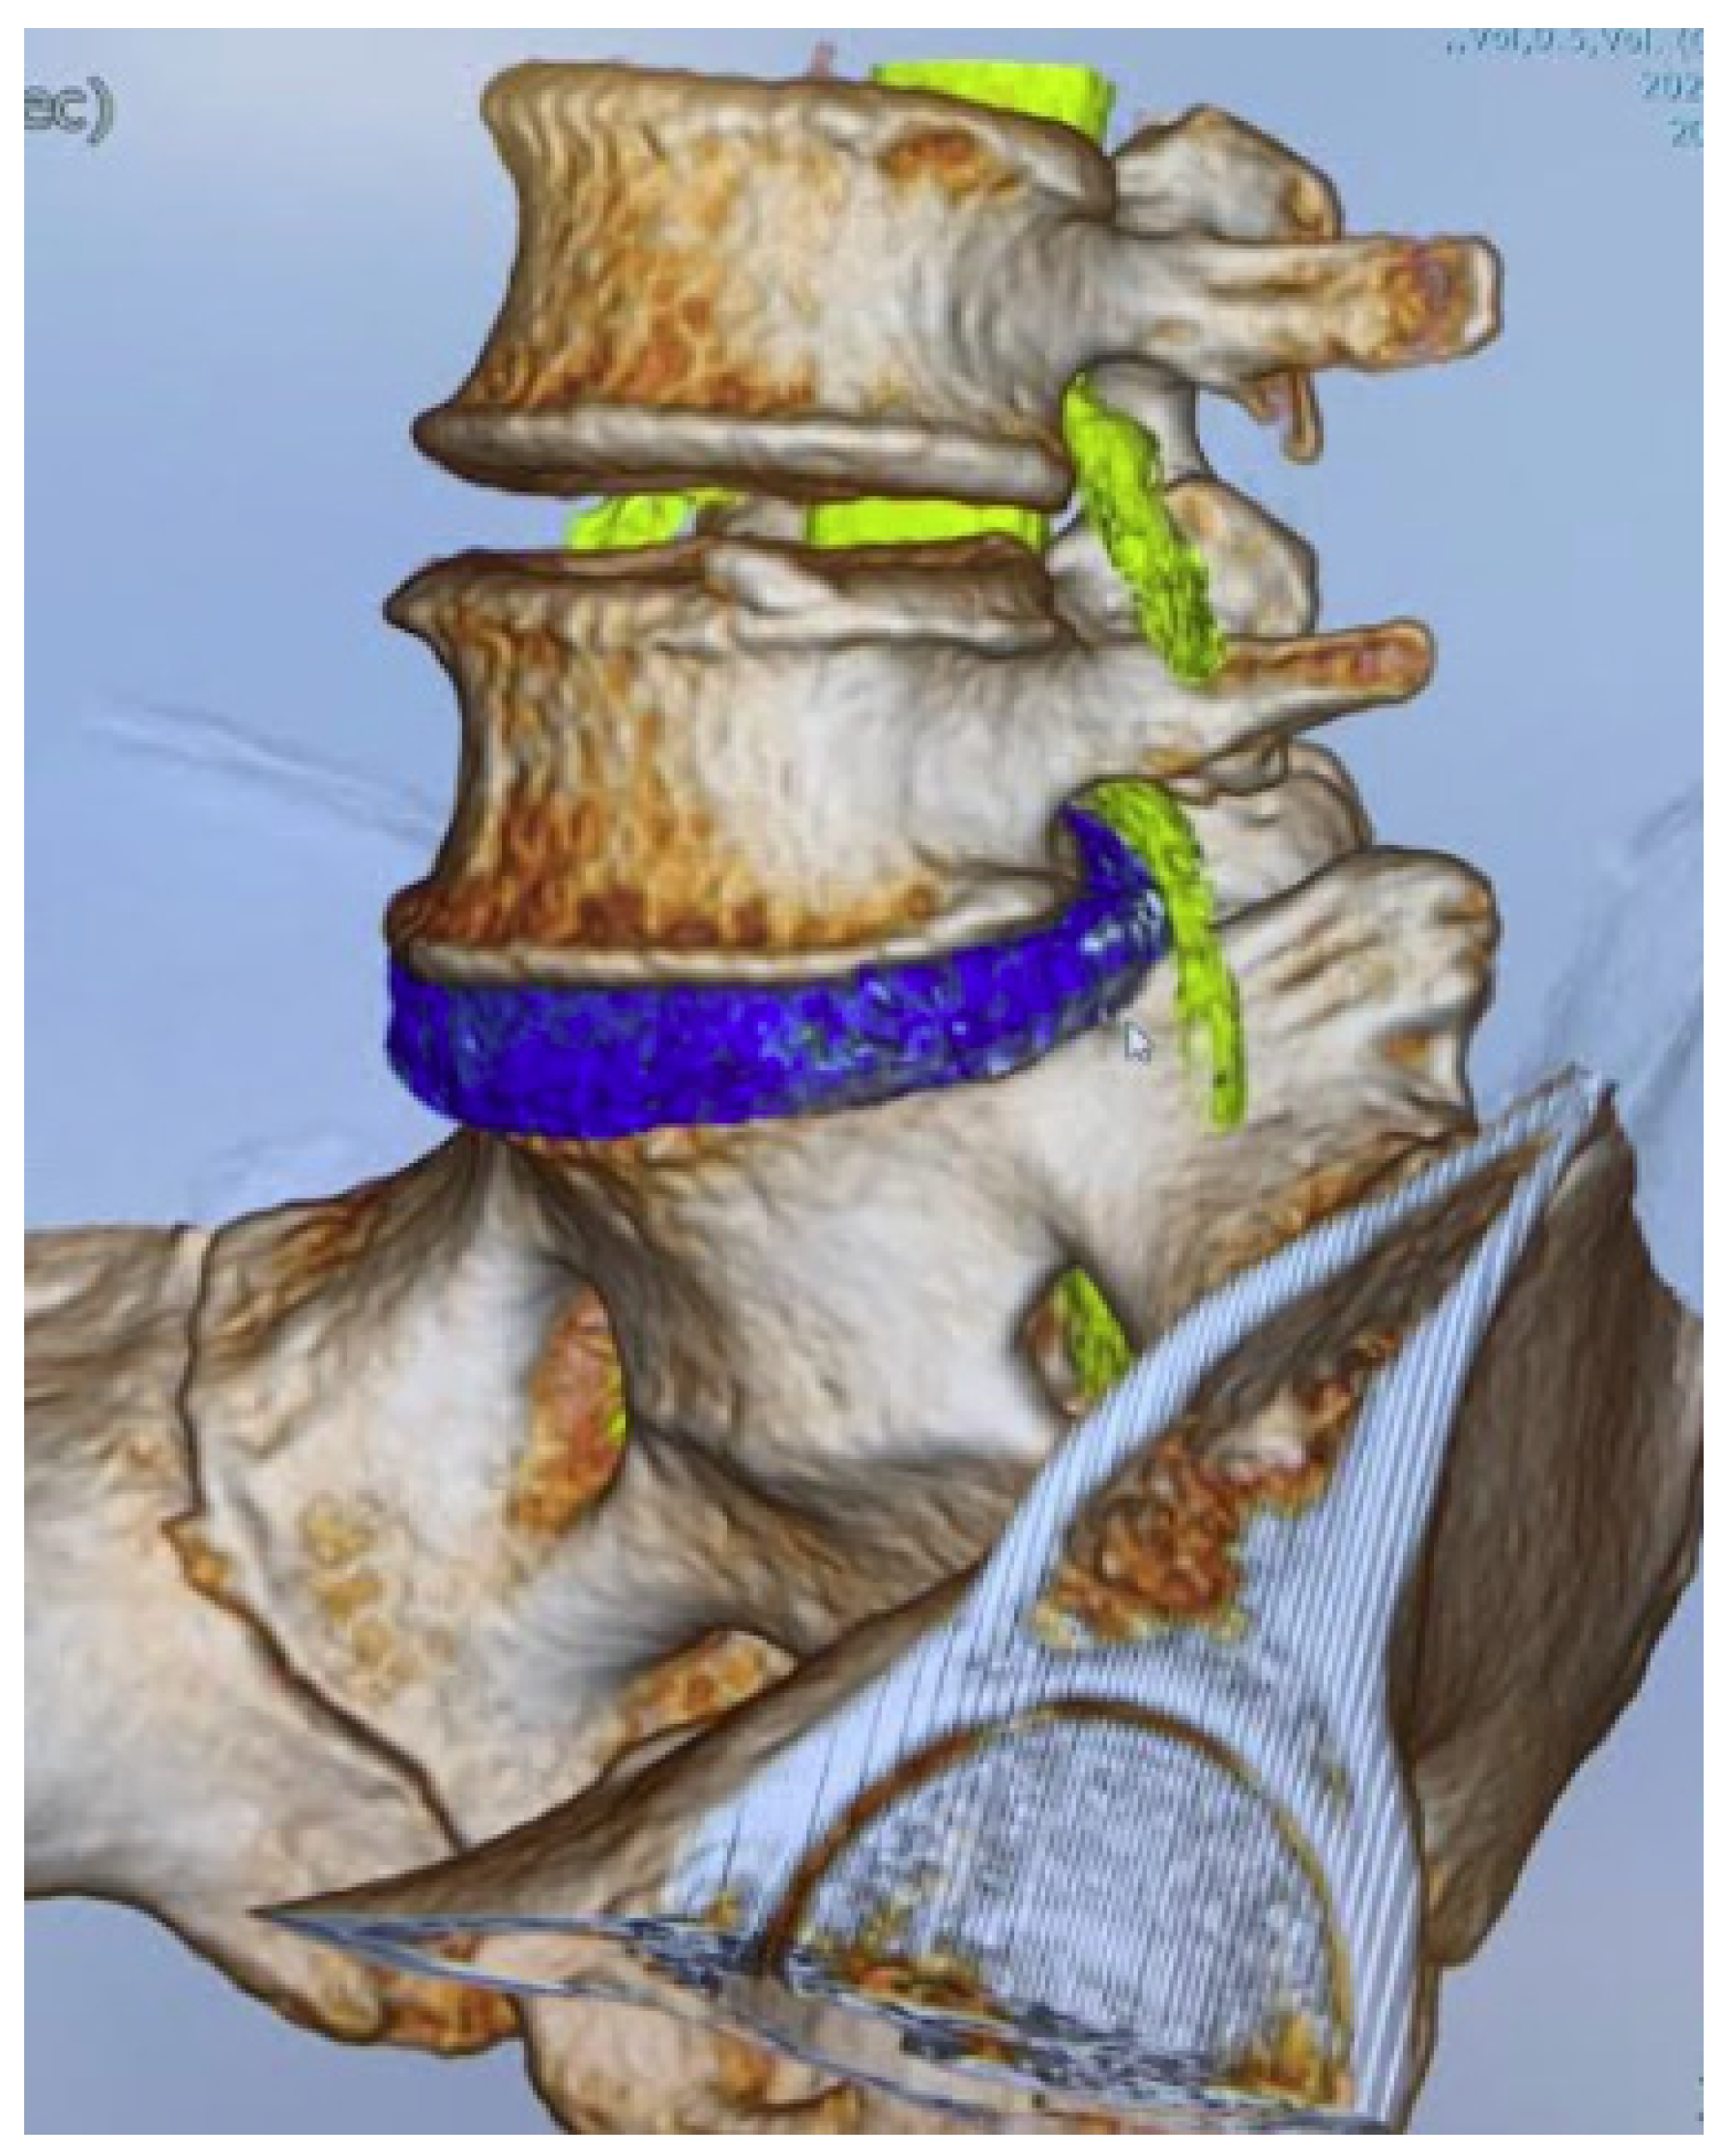

2.3. CT-MRI Fusion Image

2.4. Evaluation of Merged Images

3.5. Herniated Disc Visualization